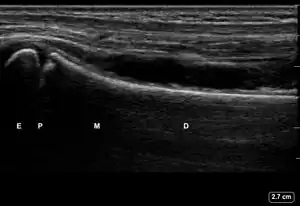

| 2 | Buckle (Torus) Fracture | "Bent" | ![]() Ultrasound dorsal view of buckle fracture of radius (shown by arrow). E = epiphysis; P = physis; M = metaphysis; D = diaphysis. | ||